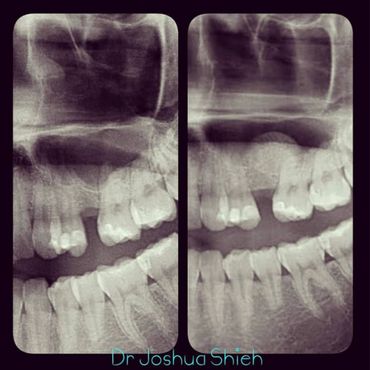

3. Preserve the remaining jaw bone and prevent resorption.